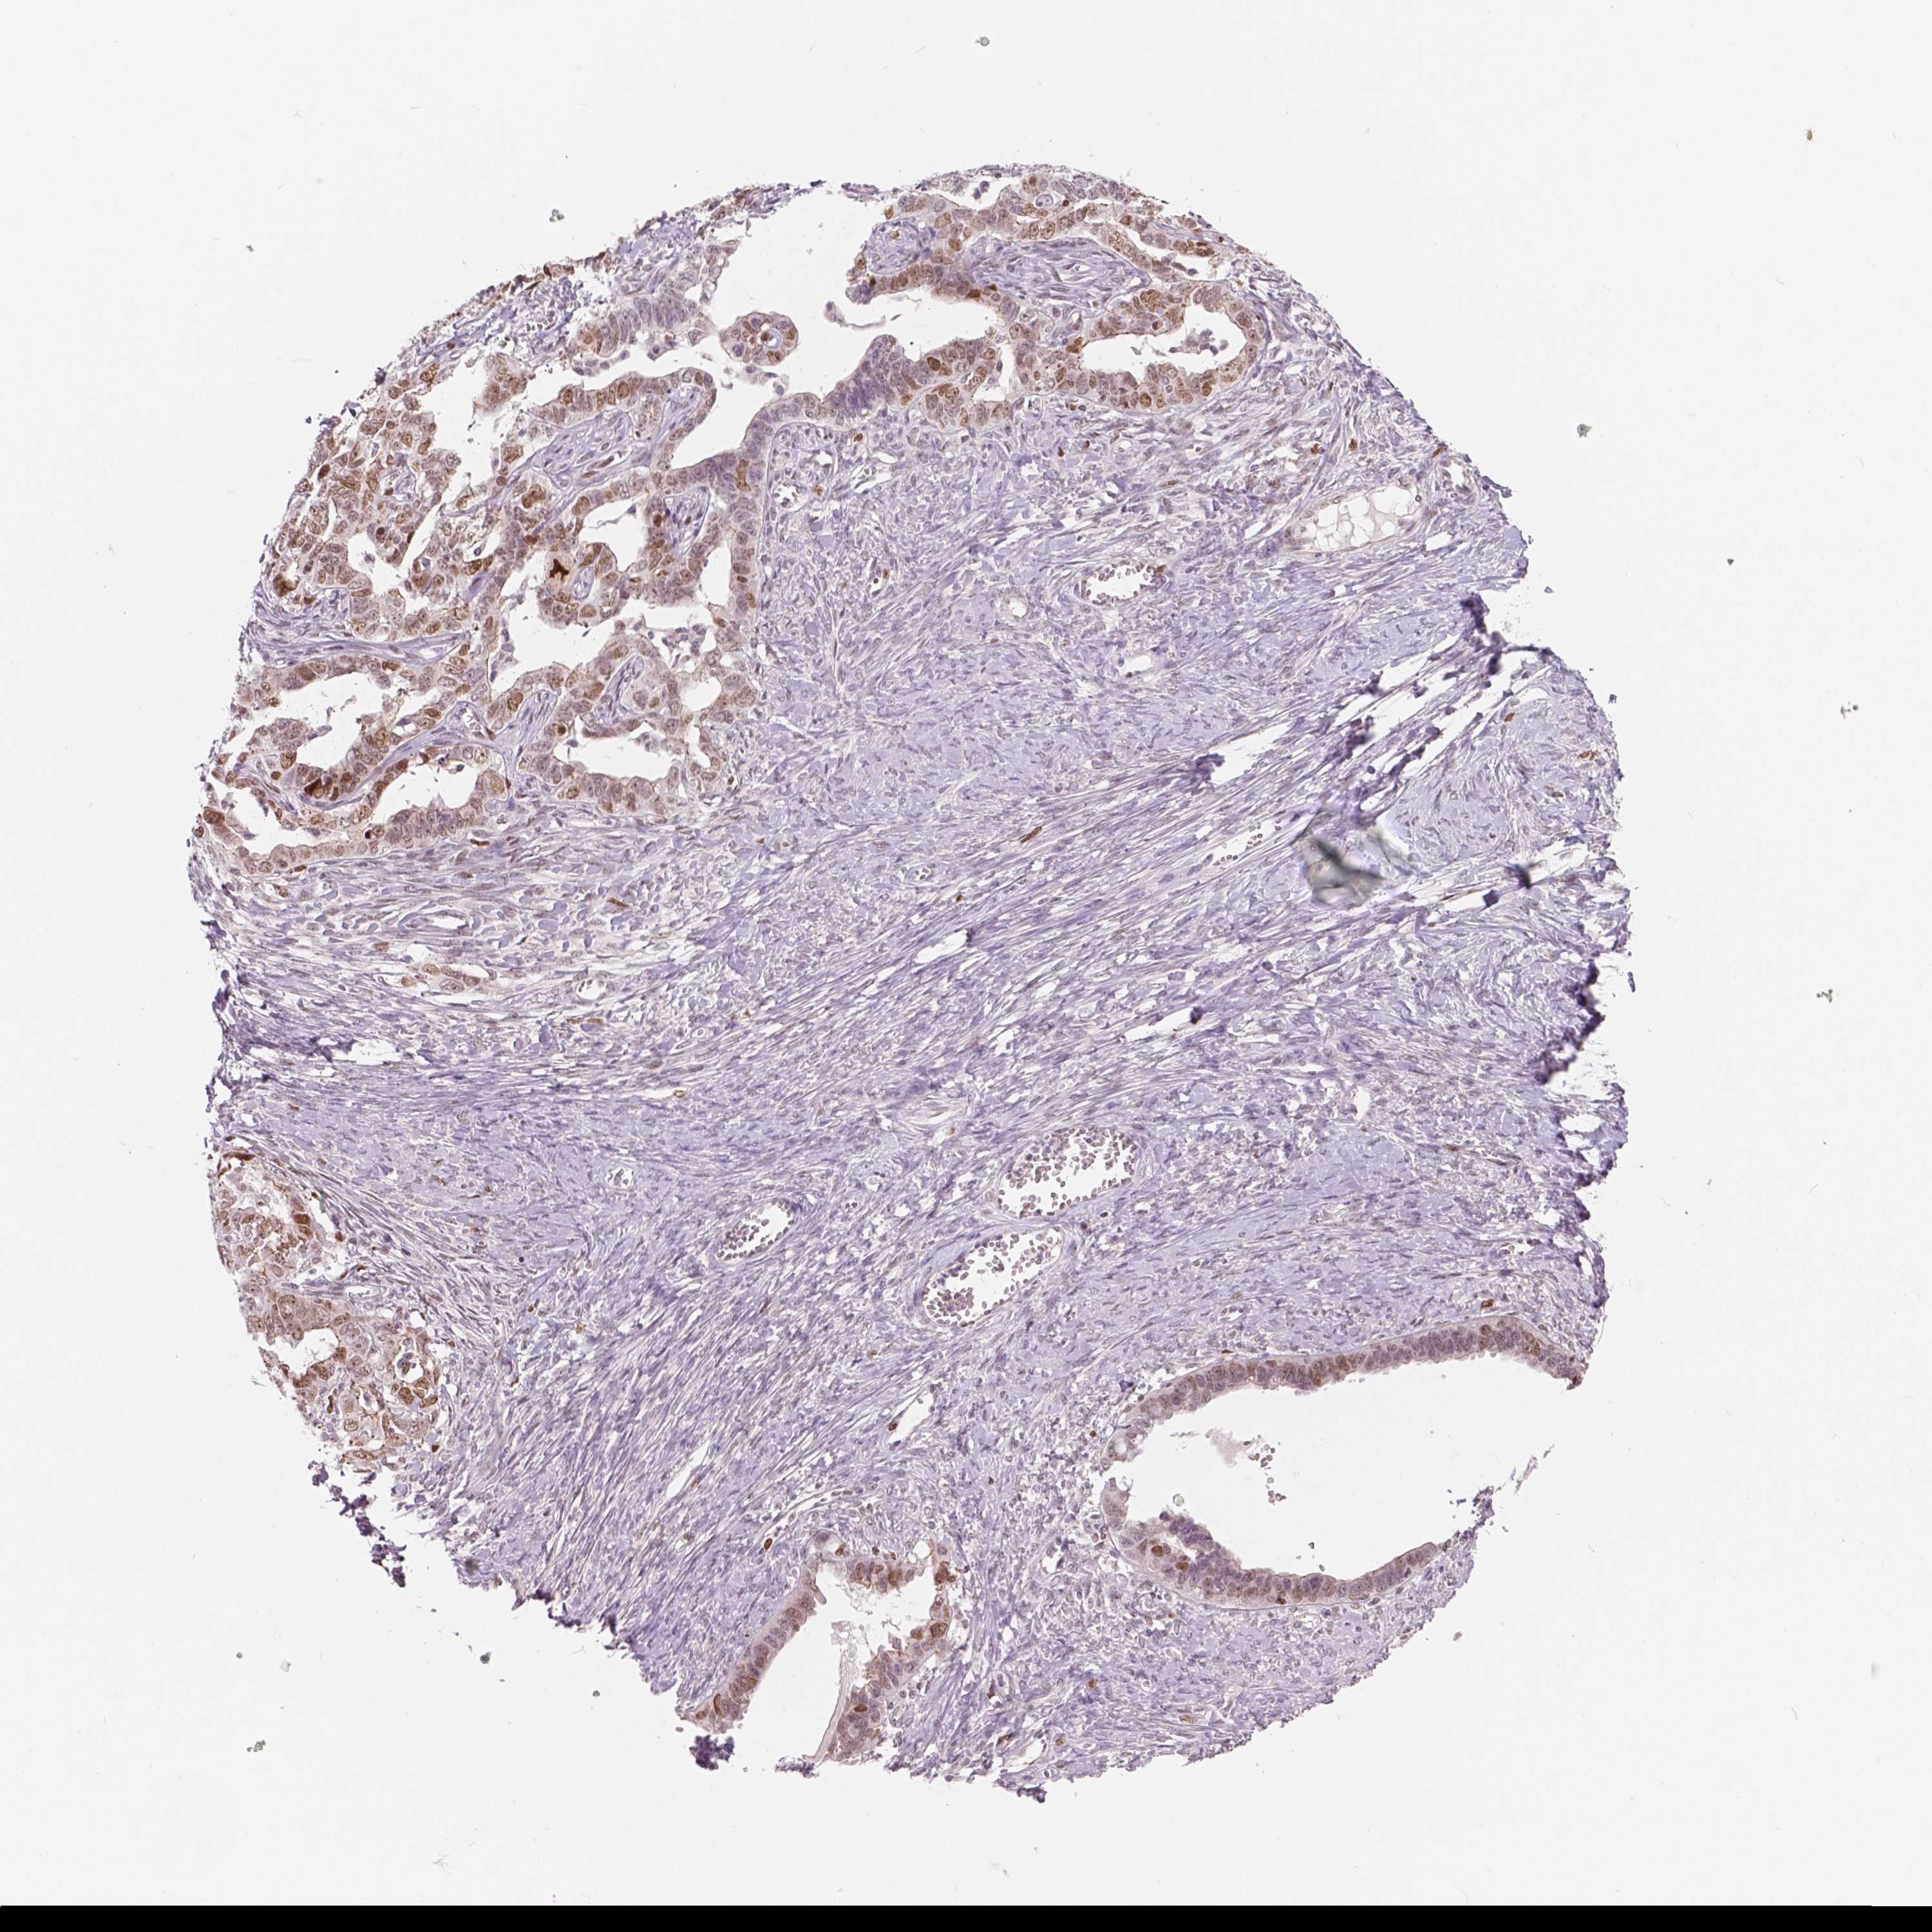

OVARIAN CANCER - Protein expressioni

A mouse-over function shows sample information and annotation data. Click on an image to view it in a full screen mode. Samples can be filtered based on level of antibody staining by selecting one or several of the following categories: high, medium, low and not detected. The assay and annotation is described here.

Note that samples used for immunohistochemistry by the Human Protein Atlas do not correspond to samples in the TCGA dataset.

Antibody stainingi

Antibody staining in the annotated cell types in the current human tissue is reported as not detected, low, medium, or high, based on conventional immunohistochemistry profiling in selected tissues. This score is based on the combination of the staining intensity and fraction of stained cells.

Each image is clickable and will lead to virtual microscopy that enables deeper exploration of all samples and also displays staining intensity scores, fraction scores and subcellular localization as well as patient and tissue information for each sample.

Antibody HPA015801

Antibody CAB068246

Antibody CAB068247

Staining

High

Medium

Low

Not detected

Intensity

Strong

Moderate

Weak

Negative

Quantity

>75%

75%-25%

<25%

None

Location

Nuclear

Cytoplasmic/membranous

Cytoplasmic/membranous,nuclear

Cystadenocarcinoma, serous, NOS

Cystadenocarcinoma, mucinous, NOS

Carcinoma, endometroid